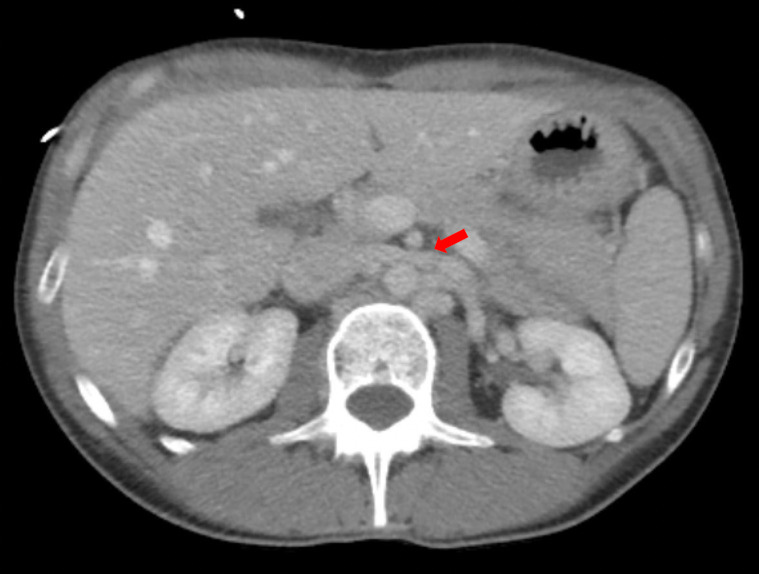

On hospital Day 1, an esophagogastroduodenoscopy (EGD) with nasogastric tube placement was completed with removal of approximately two liters of chyme (i.e., acidic gastric fluid). Initial computer tomography was reviewed by Radiology, and SMAS was diagnosed (Images 1 and 2). After a multidisciplinary review consisting of the case’s internal medicine, gastroenterology and general surgery teams, the patient was transferred to a tertiary care center where a gastrostomy-jejunostomy tube was placed. She was started on tube feedings and reported improvement of symptoms at follow-up one month later.

Pertinent findings on physical exam included mid-epigastric abdominal pain with an underweight BMI of 18.6. Computer tomography of the abdomen and pelvis with intravenous contrast provided a radiological diagnosis of SMAS (Images 3 and 4).